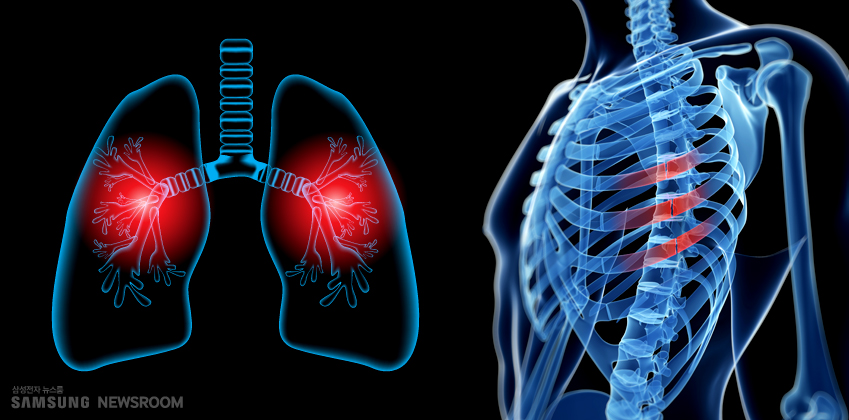

가슴이 좁아지는 듯한 느낌과 통증을 느끼기 때문에 협심증이라 불러요. 협심증은 심장에 혈액을 공급해주는 관상 동맥이 좁아져 충분한 혈액공급이 이루어지지 않아 발생되는 가슴통증을 말하는 질환인데요. 관상동맥이 좁아지는 동맥 경화증은 20대 초반부터 시작되며 혈관이 약 70% 이상 좁아지면 협심증 증상이 발생하게 됩니다.

흉부 부근에 압박감이 나타나는 것이 대표적인 협심증 초기증상이라고 해요. 호흡곤란이나 흉통 증상의 경우 수분 정도 지속되다가 다시 없어지는 경우도 있다고 하네요. 보통은 날이 추운 겨울철이나 과도한 활동 시에 심장에 산소가 많이 필요한 상황이 되면 협심증 초기증상을 경험하게 돼요. 보통 가슴 가운데에 압박감이 느껴지며 답답한 느낌을 느끼고 호흡이 힘들어질 수도 있어요.

가장 흔히 발생하는 협심증 초기 증상은 가슴 통증인 흉통인데요. 가슴의 정중앙이나 약간 좌측 부위에서 주로 나타나고 가슴에 쥐어짜는 듯한 통증이나 가슴이 쌔한 느낌이 드는데 가슴 통증 이외에도 명치가 아프거나 턱끝이 아프다고 하는 경우도 있고, 위 부분이 아픈 경우도 있어요.